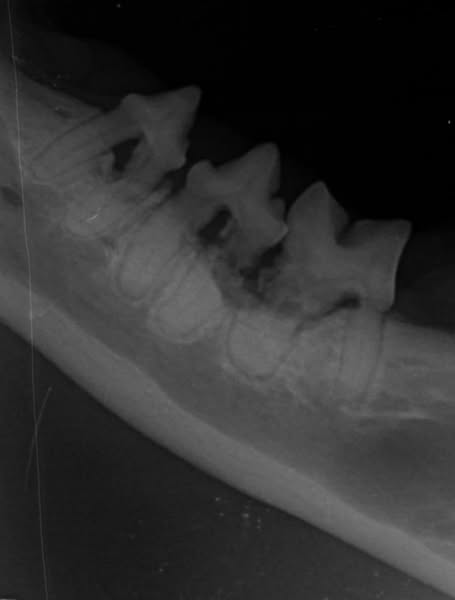

在手術前也會先拍攝全口X光做為術前的評估,手術中也要使用牙科探針的檢查,才不會漏失掉病灶喔!在萌寵還有使用人醫等級的牙科超音波骨刀,應用在寵物牙科手術,可以大幅縮短手術的時間及疼痛感!